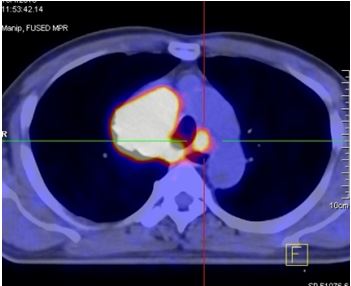

- Hình ảnh PET/CT:

Kết quả PET/CT: Hình ảnh khối u thùy trên phổi phải (mũi tên đỏ) kích thước 5,6x6,9x9,0cm, tăng hấp thu F-18 FDG, max SUV=13,18, chèn ép làm hẹp lòng khí quản, hạch lớn trung thất tăng hấp thu F-18 FDG. Tổn thương đốt sống D2 (mũi tên vàng) tăng hấp thu F-18 FDG, max SUV=8,85. |